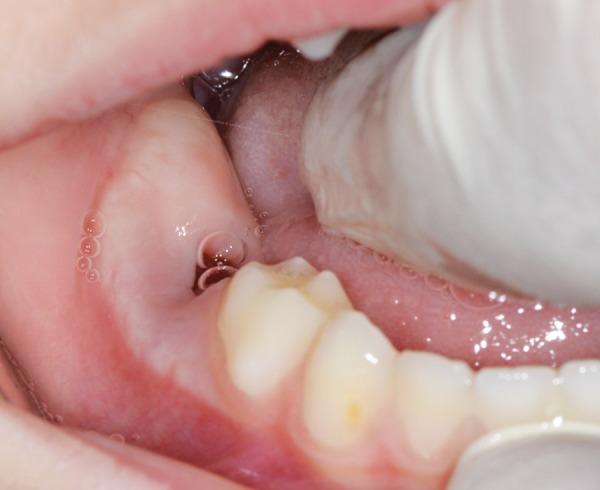

Hidden caries is a dentinal lesion beneath the dentinoenamel junction, visible on radiographs. A single report described this lesion in primary dentition. This case report describes a case of hidden caries in a mandibular second primary molar, misdiagnosed as malignant swelling. A 3-year-old white girl was referred to the Department of Pediatric Dentistry with a chief complaint of pain and extraoral swelling on the right side of the mandible for the last 3 months. She was earlier referred to the surgical department for biopsy of the lesion. Radiographic and computed tomography scan examination showed a periapical lesion with buccal plate resorption and radiolucency beneath the enamel on the mesial part of tooth 85. The tooth was extracted, and follow-up of 2 years showed normal development of tooth 45. The main problem is early detection and treatment, since the outer surface of enamel may appear intact on tactile examination.

隐匿性龋是位于牙本质釉质界下方的牙本质病变,在X线片上可见。有一份报告描述了乳牙列中的这种病变。本病例报告描述了一例下颌第二乳磨牙隐匿性龋被误诊为恶性肿胀的病例。一名3岁白人女孩因右侧下颌疼痛和口外肿胀3个月为主诉被转诊至儿童牙科。她之前被转诊至外科进行病变活检。X线片和计算机断层扫描检查显示85号牙近中部分根尖周病变伴颊侧板吸收以及釉质下方的透射区。该牙被拔除,2年的随访显示45号牙发育正常。主要问题是早期发现和治疗,因为在触诊检查时釉质外表面可能看起来完好无损。